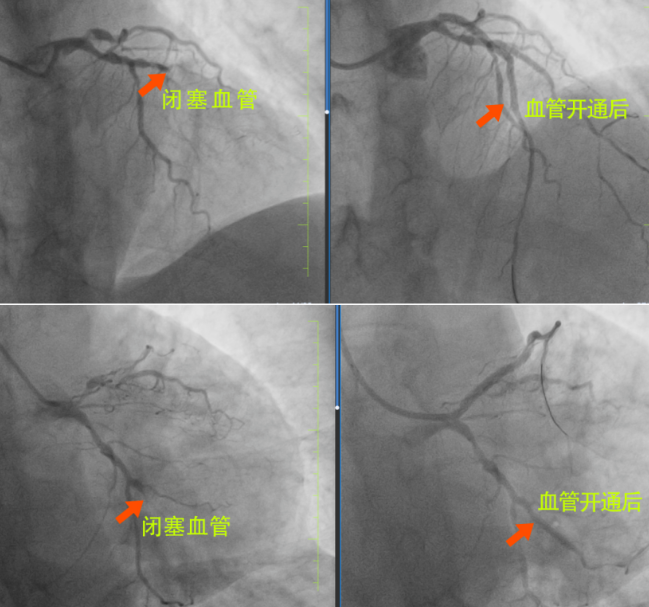

很快,長春國文醫(yī)院心內(nèi)科為患者安排了手術(shù),為患者進行手術(shù)的是長春國文醫(yī)院副院長、心血管中心主任隋立有。隋院長在心血管領(lǐng)域造詣深厚,擁有豐富的臨床經(jīng)驗。隋院長始終專注于心血管疾病的研究與治療,對各類復(fù)雜心血管病例有著獨到的見解和精準(zhǔn)的判斷。隋院長在了解患者的病情后,迅速制定了治療方案。患者3根血管完全閉塞,情況十分危急。但隋院長憑借著精湛的醫(yī)術(shù)和豐富的經(jīng)驗,巧妙地開通了2根血管,整個手術(shù)過程僅僅用了不到半小時,就成功完成了3枚支架的植入。這一高效且精準(zhǔn)的手術(shù),讓患者和家屬驚嘆不已,也讓他們真切地感受到了國文醫(yī)院心內(nèi)科雄厚的師資力量和成熟的技術(shù)實力。